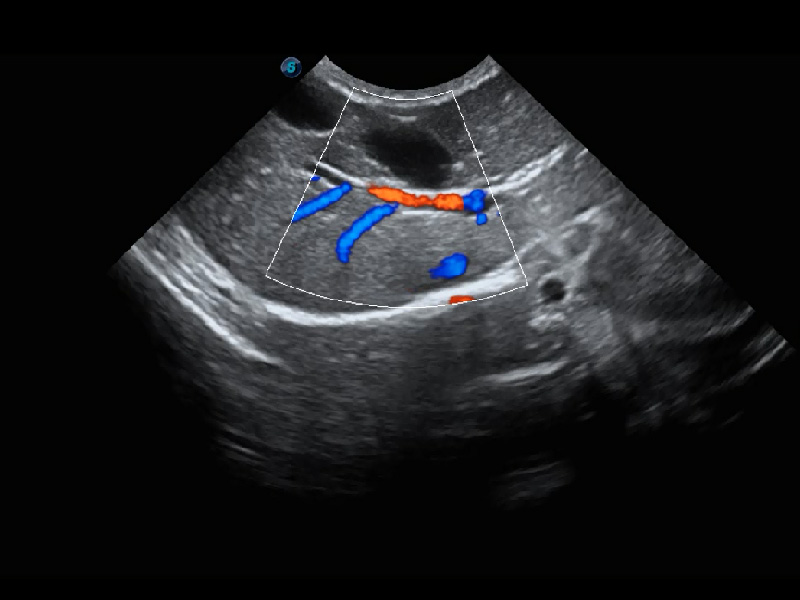

(犬)肾脏血流